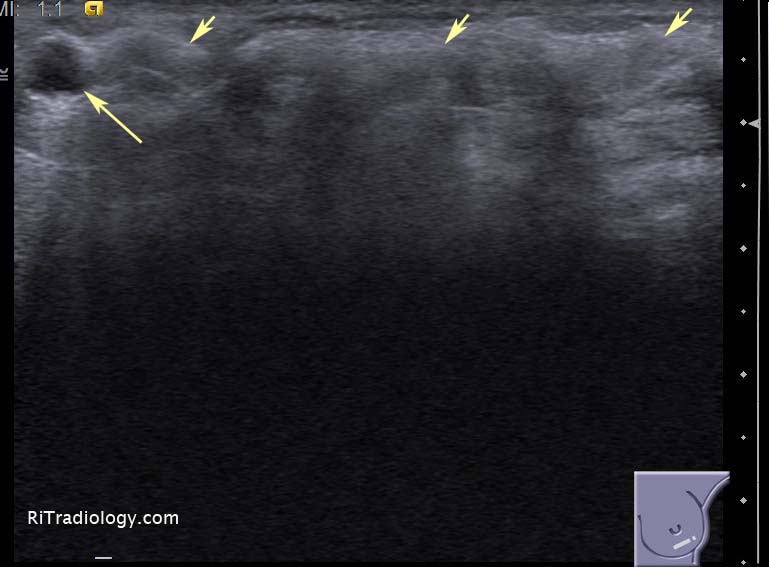

El ultrasonido es superior en la visualización de tejidos mamarios densos, donde las mamografías pueden no ser tan efectivas debido a la superposición de tejidos que dificulta la detección de tumores. Esto hace que el ultrasonido sea una herramienta complementaria importante en el diagnóstico de cáncer de mama en mujeres jóvenes o en aquellas con tejido mamario denso.

Mientras que la mamografía es ideal para detectar microcalcificaciones que pueden ser indicativas de cáncer, el ultrasonido es mejor para distinguir entre lesiones sólidas y quísticas. Además, el ultrasonido puede proporcionar información sobre el flujo sanguíneo en las lesiones mamarias mediante el uso de la ecografía Doppler, una funcionalidad que no está disponible en la mamografía.